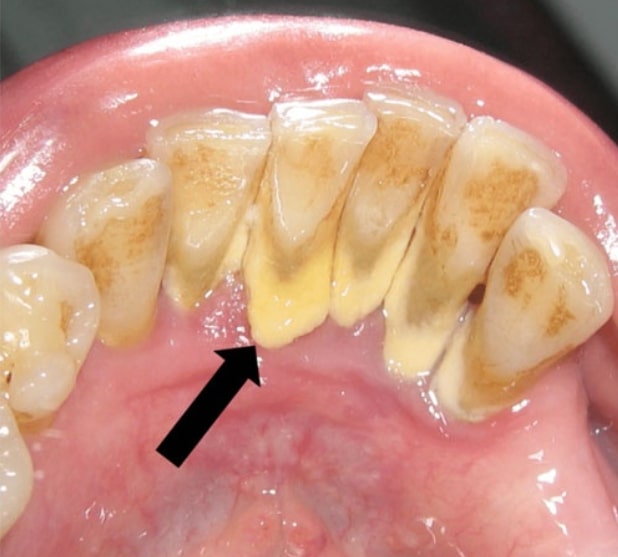

Cao răng là những mảng bám cứng, có màu trắng/vàng/nâu, bám quanh chân răng hoặc trên bề mặt răng. Xét về mặt khoa học, đó là sự tích tụ của các thành phần như canxi carbonat, chất khoáng, cặn thức ăn, vi khuẩn, xác tế bào chết… Cao răng thường thấy nhiều ở mặt trong răng hoặc kẽ răng, nơi mọi người ít chải kĩ.

Cao răng hình thành trong quá trình ăn uống hằng ngày. Cặn thức ăn được xúc tác bởi vi khuẩn, nước bọt cùng các khoáng chất tạo nên các mảng bám trên bề mặt răng. Mảng bám không được vệ sinh đúng cách sẽ kết hợp với các hợp chất muối tạo thành cao răng.

Nếu không lấy cao răng độc tố của các vi khuẩn trong cao răng sẽ gây ra phản ứng viêm tại chỗ. Từ đó gây nên các bệnh lý như viêm lợi, viêm quanh răng, thậm chí lung lay răng và mất răng. Việc vệ sinh răng miệng đúng cách và lấy cao răng định kì sẽ không chỉ giúp răng miệng sáng bóng, giữ gìn hơi thở thơm tho mà còn phòng tránh những bệnh lý nguy hiểm trên.